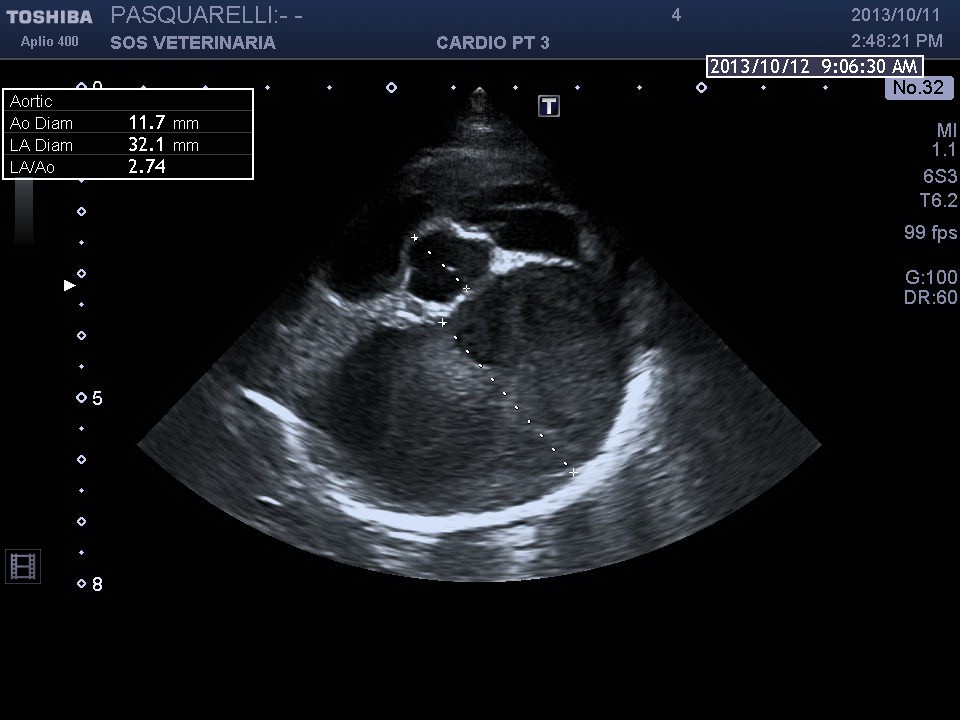

caso di cardiomiopatia ipertrofica del Maine Coone ,presentazione al pronto soccorso tipica con edema polmonare e tromboembolismo aortico completo bilaterale ,per la mia esperienza,nessun trattamento risulta essere efficace per questi soggetti, il decesso avviene nel 90%-95% dei casi e quelli che sopravvivono muoiono nelle settimane successive per le severe complicanze provocate dall’ipoperfusione ,i trattamenti trombolitici non risultano praticabili per diverse ragioni, non ultima quella economica, l’evento drammatico non e’ lo scompenso cardiaco diastolico (sul piano farmacologico gestibile) ma la trombosi aortica spesso anche polmonare .

Per avere una idea del grado di pericolosita’ della malattia basta visionare lo smoke (effetto fumo) nell’atrio sx del soggetto e il voluminoso trombo fluttuante e martellante i lembi valvolari .

Una diagnosi precoce e una corretta terapia antiaggregante avrebbe consentito a questo soggetto di vivere tranquillamente fino allo scompenso congestizio diastolico inevitabile con l’aumentare del grado di ipertrofia.

Il soggetto aveva solo due anni di eta’ e aveva eseguito il test genico risultato negativo , da qui l’importanza, per una corretta analisi cardiologica ,dell’ecocardiogramma ,mai eseguito in questo caso .